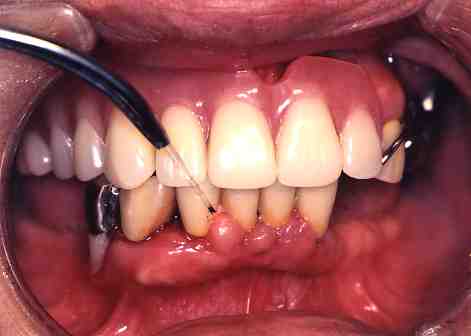

2.レーザー照射中

3.一週間後

歯の周りの歯ぐきの腫れも

かなりおさまりました。